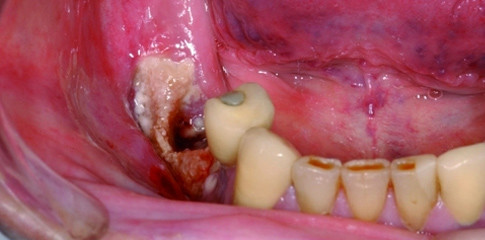

Implantologische Therapien sollten dementsprechend einer äußerst strengen Indikationsstellung unterzogen werden (Abb. 1 und 2) und auch bezüglich des Therapieablaufs der stattgefundenen oder geplanten Bisphosphonattherapie ist eine ausführliche Anamnese unerlässlich. Patienten mit bereits vor Beginn einer Bisphosphonattherapie inserierten Implantaten bedürfen einer intensivierten Nachsorge, da die Implantatdurchtrittsstellen einen Locus minor resistentiae darstellen können (Abb. 3). Insgesamt lässt sich absehen, dass bei Bisphosphonattherapien aus osteologischer Indikation (hauptsächlich bei der Osteoporose) weniger Knochennekrosen zu verzeichnen sind als bei Therapien aus onkologischer Indikation. Häufig werden bei Patienten mit malignen Erkrankungen die Präparate Zoledronat (Zometa®), Pamidronat (Aredia®) und Ibandronat (Bondronat®) intravenös verabreicht, bei Osteoporosen häufig die Präparate Ibandronat (Bonviva®), Alendronat (Fosamax®), Risedronat (Actonel®), Tiludronat (Skelid®), Clodronat (Ostac®, Bonefos®) und Etidronat (Didronel®, Diphos®) in oraler Form. Da die betroffenen Patienten leider oft selbst nicht wissen, ob sie ein Bisphosphonat einnehmen oder eingenommen haben, empfiehlt es sich die Medikamentenanamnese sorgfältig zu erheben und auf die oben genannten Präparate hin zu überprüfen.

Der Patient stellte sich nun mit einer nach dem zweiten Eingriff erneut gelockerten Osteosynthese vor. Die Frakturenden waren stark disloziert, es imponierte ein nach intra- und nach extraoral freiliegender Knochen mit Fistelung von Intra- nach Extraoral und Ausfluss von Pus sowie eine ausgedehnte Osteonekrose (Abb. 6 bis 8).

Zum Zeitpunkt der Erstvorstellung der Patientin, die dann notfallmäßig erfolgte, imponierte eine massiv entzündete und dislozierte pathologische Fraktur mit Fistelung und Pusaustritt nach extraoral sowie eine ausgedehnte Entzündung der umliegenden Weichgewebe (Abb. 17). Die Implantate in Regio 45 und 46 zeigten eine periimplantäre Entzündung und Lockerung (Abb. 16 und 18).